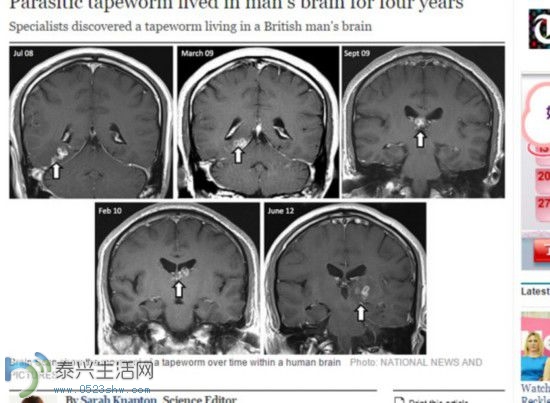

英男子头痛4年 检查发现寄生虫从其右脑爬到左脑 |